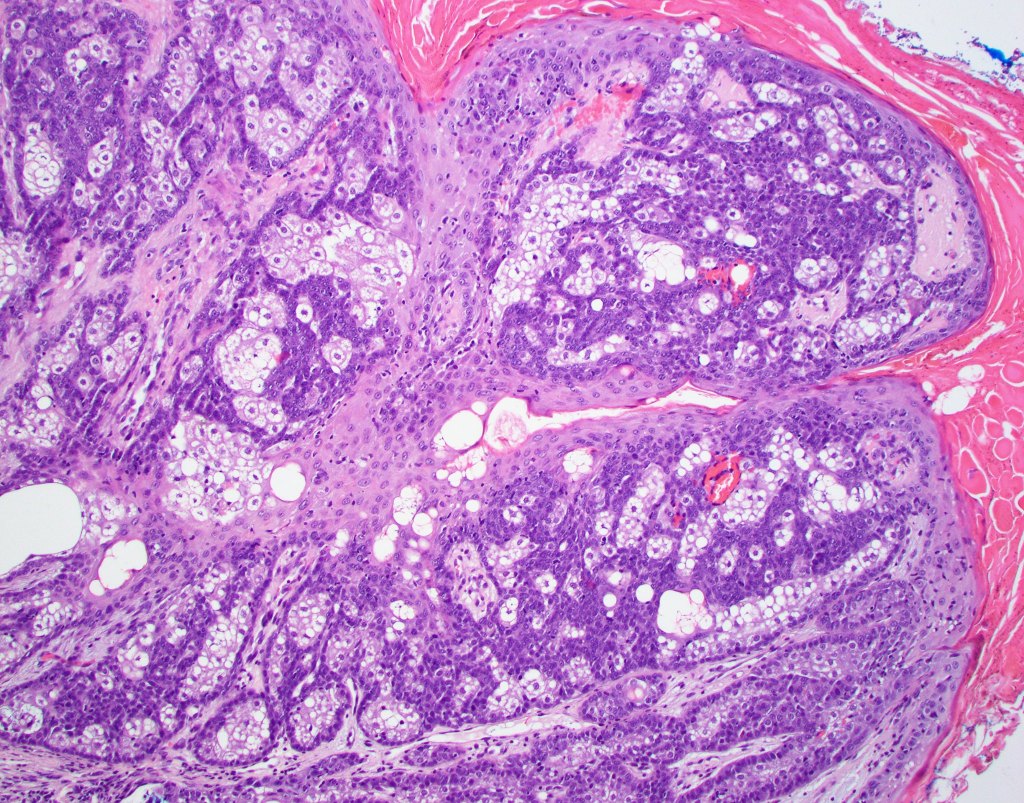

Histological features

•Variable continuity with epidermis

•Multinodular with surrounding collagenous stroma

•Random distribution of basaloid cells & sebocytes (<50% sebocytes)

•Duct formation, often with holocrine secretion generally present

•Mitoses sparse to conspicuous

•Absent peripheral palisading & retraction artifact

•Cystic variant

•Subtypes include rippled pattern, carcinoid-like & reticulated